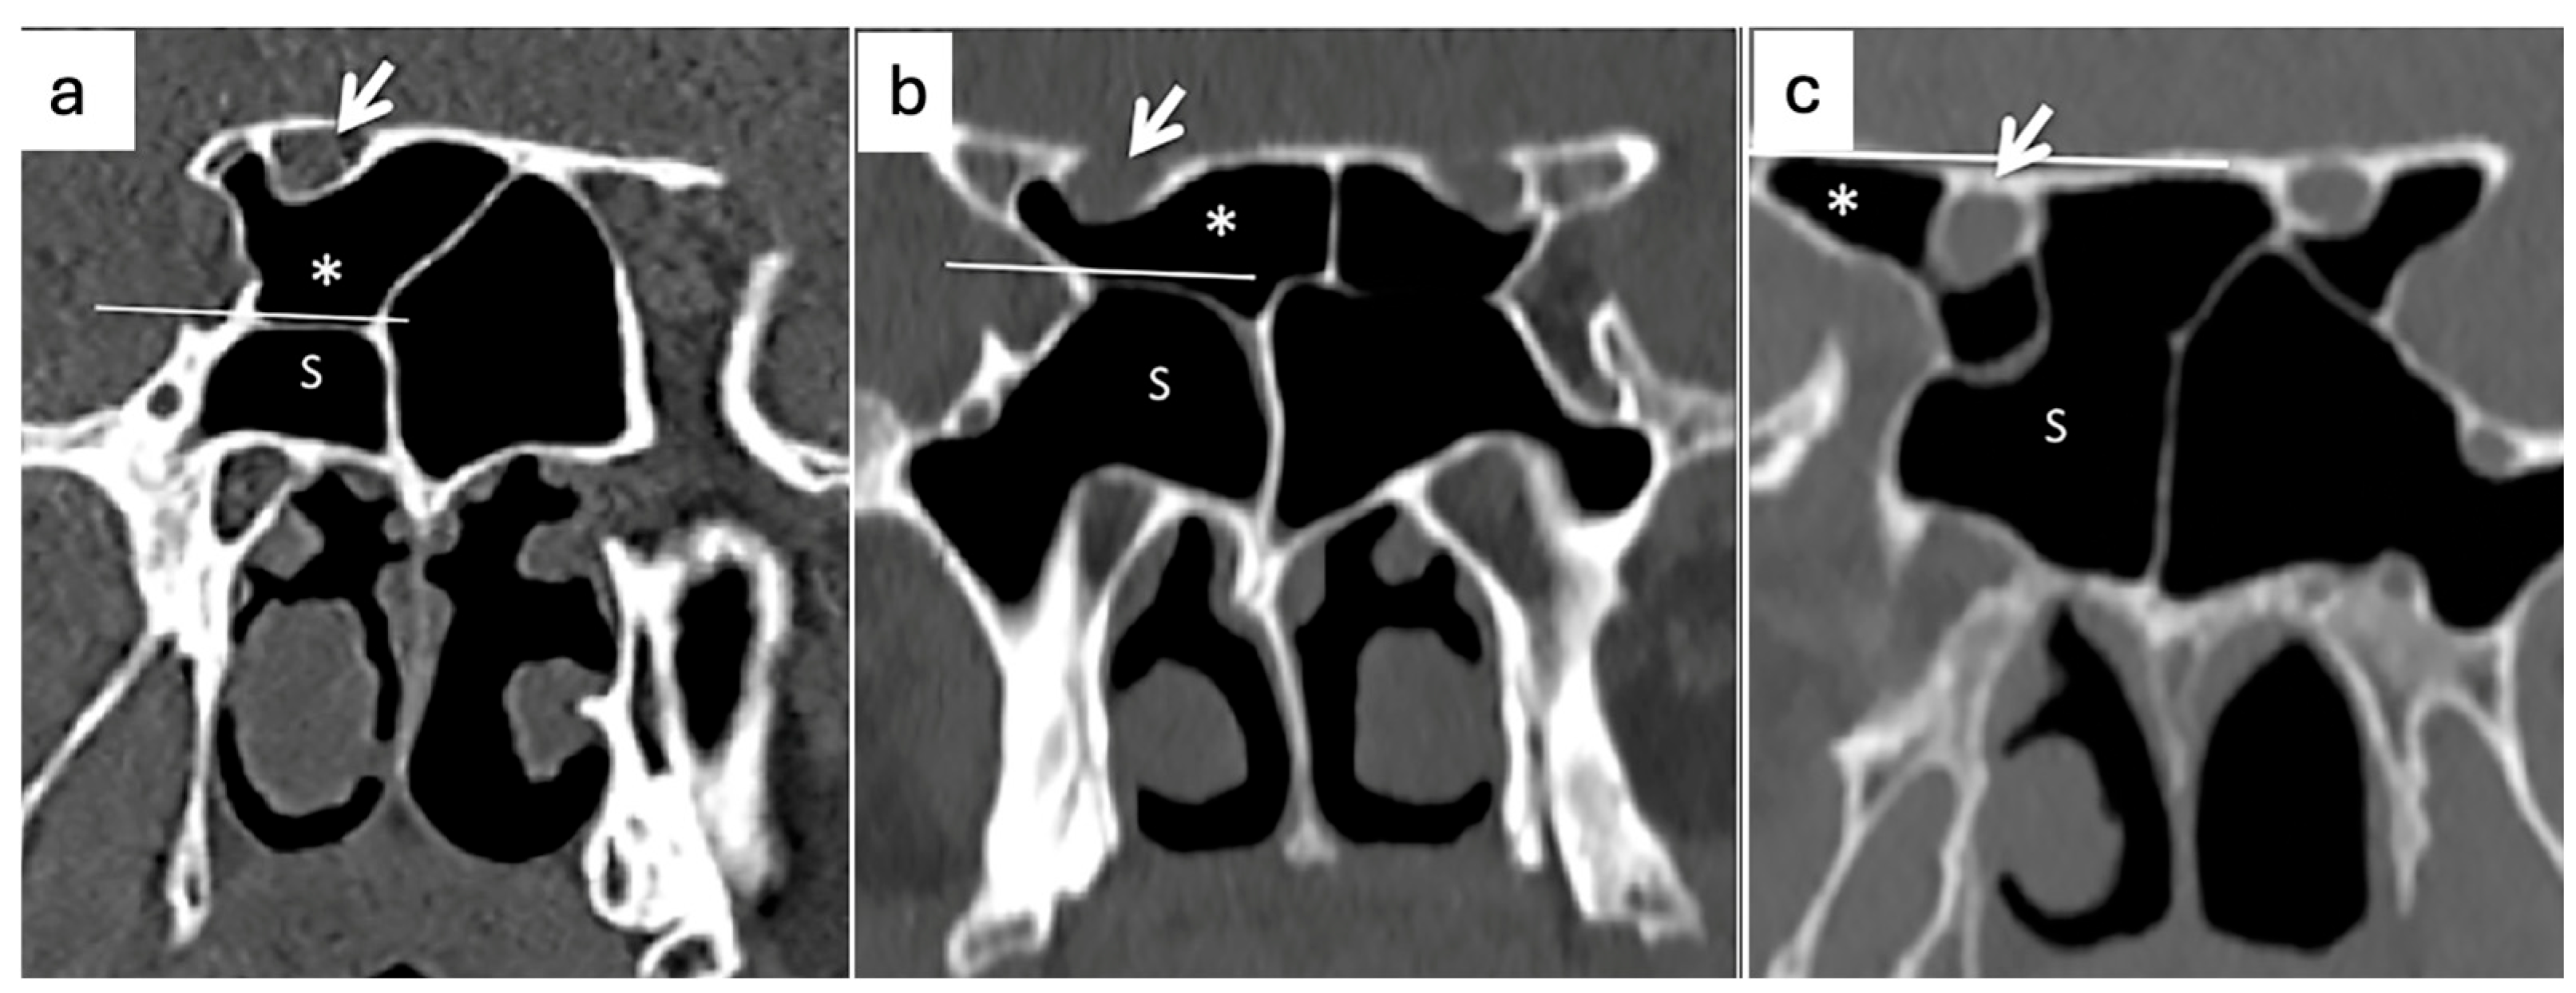

- Wada, K.; Moriyama, H.; Edamatsu, H.; Hama, T.; Arai, C.; Kojima, H.; Otori, N.; Yanagi, K. Identification of Onodi cell and new classification of sphenoid sinus for endoscopic sinus surgery. Int. Forum Allergy Rhinol. 2015, 5, 1068–1076. [Google Scholar] [CrossRef] [PubMed]

- Chmielik, L.P.; Chmielik, A. The prevalence of the Onodi cell—Most suitable method of CT evaluation in its detection. Int. J. Pediatr. Otorhinolaryngol. 2017, 97, 202–205. [Google Scholar] [CrossRef] [PubMed]

- Thimmaiah, V.T.; Anupama, C. Pneumatization patterns of Onodi cell on multidetector computed tomography. J. Oral. Maxillofac. Radiol. 2017, 5, 63–66. [Google Scholar] [CrossRef]